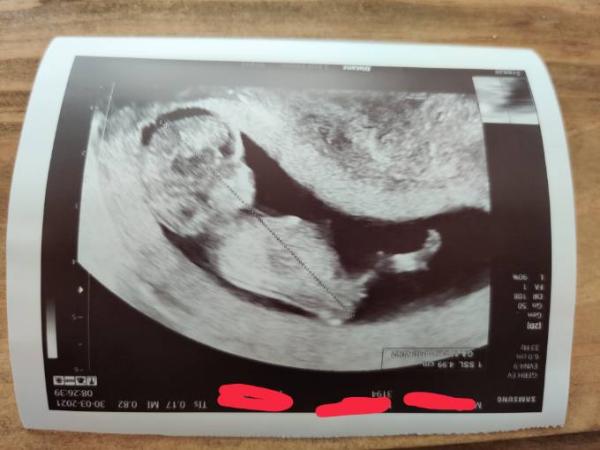

Hallo und guten Morgen , Vielleicht hat jemand den siebten Sinn oder Erfahrung mit deuten von Geschlechtern. Also ich kann da gar nichts erkennen . Vielen Dank ...und ja für uns ist die Gesundheit des Kindes an Nummer 1. Jedoch etwas hibbrln darf man ja

Bild zu Mädchen oder Junge? - Schwanger - wer noch? Rund um die Schwangerschaft

Davon mal abgesehen, dass es viel zu früh ist und man nichts erkennen kann ist die Position auch falsch, da müsstest du schon ein Foto von unten haben und selbst dann wäre es 50/50.

Hallo! Damit man überhaupt was erkennen kann, muss man das Foto von unten machen, wo Baby auf Popo sitzt

Abgesehen davon, dass man so nichts erkennen kann, finde ich es wichtig, sich klar zu machen, wie klein das Baby noch ist! Das hat jetzt vielleicht eine Scheitel-Steiß-Länge von 54 mm...

Hi So früh sehen die Geschlechter noch gleich aus. Wenn das Foto aus der 14 SSW wäre würde ich auf einen Jungen tippen Lg